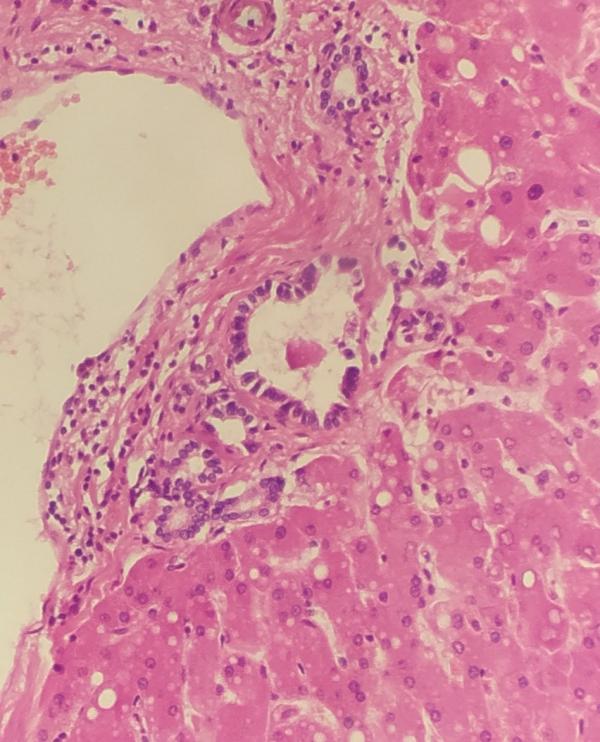

Ну и со стеклами уже лучше ориентируюсь)

Правда недавно пришлось идти к старшим коллегам, так как я не могла понять, что же с щитовидкой. Оказалось, что папиллярный рак! Но это просто находка на вскрытии, так сказать. Но интересно вск равно.